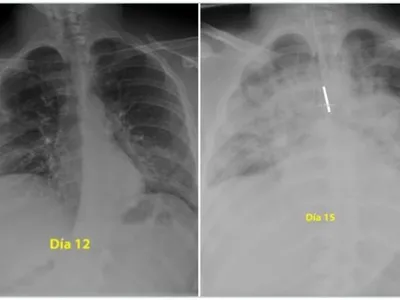

Vindecarea de infecția cu noul coronavirus se face, de cele mai multe ori, cu sechele, iar aceste sechele trebuie reevaluate periodic, avertizează Beatrice Mahler și Florin Roșu, medici care lucrează în spitale aflate în prima linie în lupta cu virusul, într-o dezbatere HotNews .